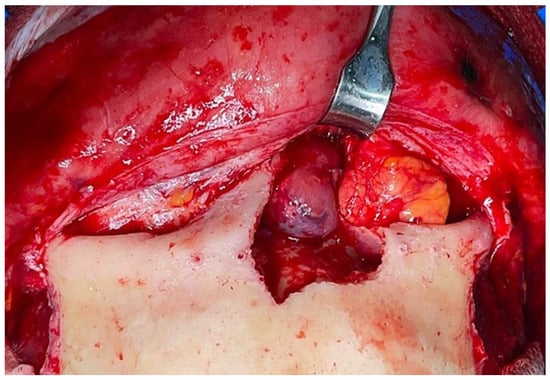

Figure 4.

Intraoperative view after complete removal of the tumor.